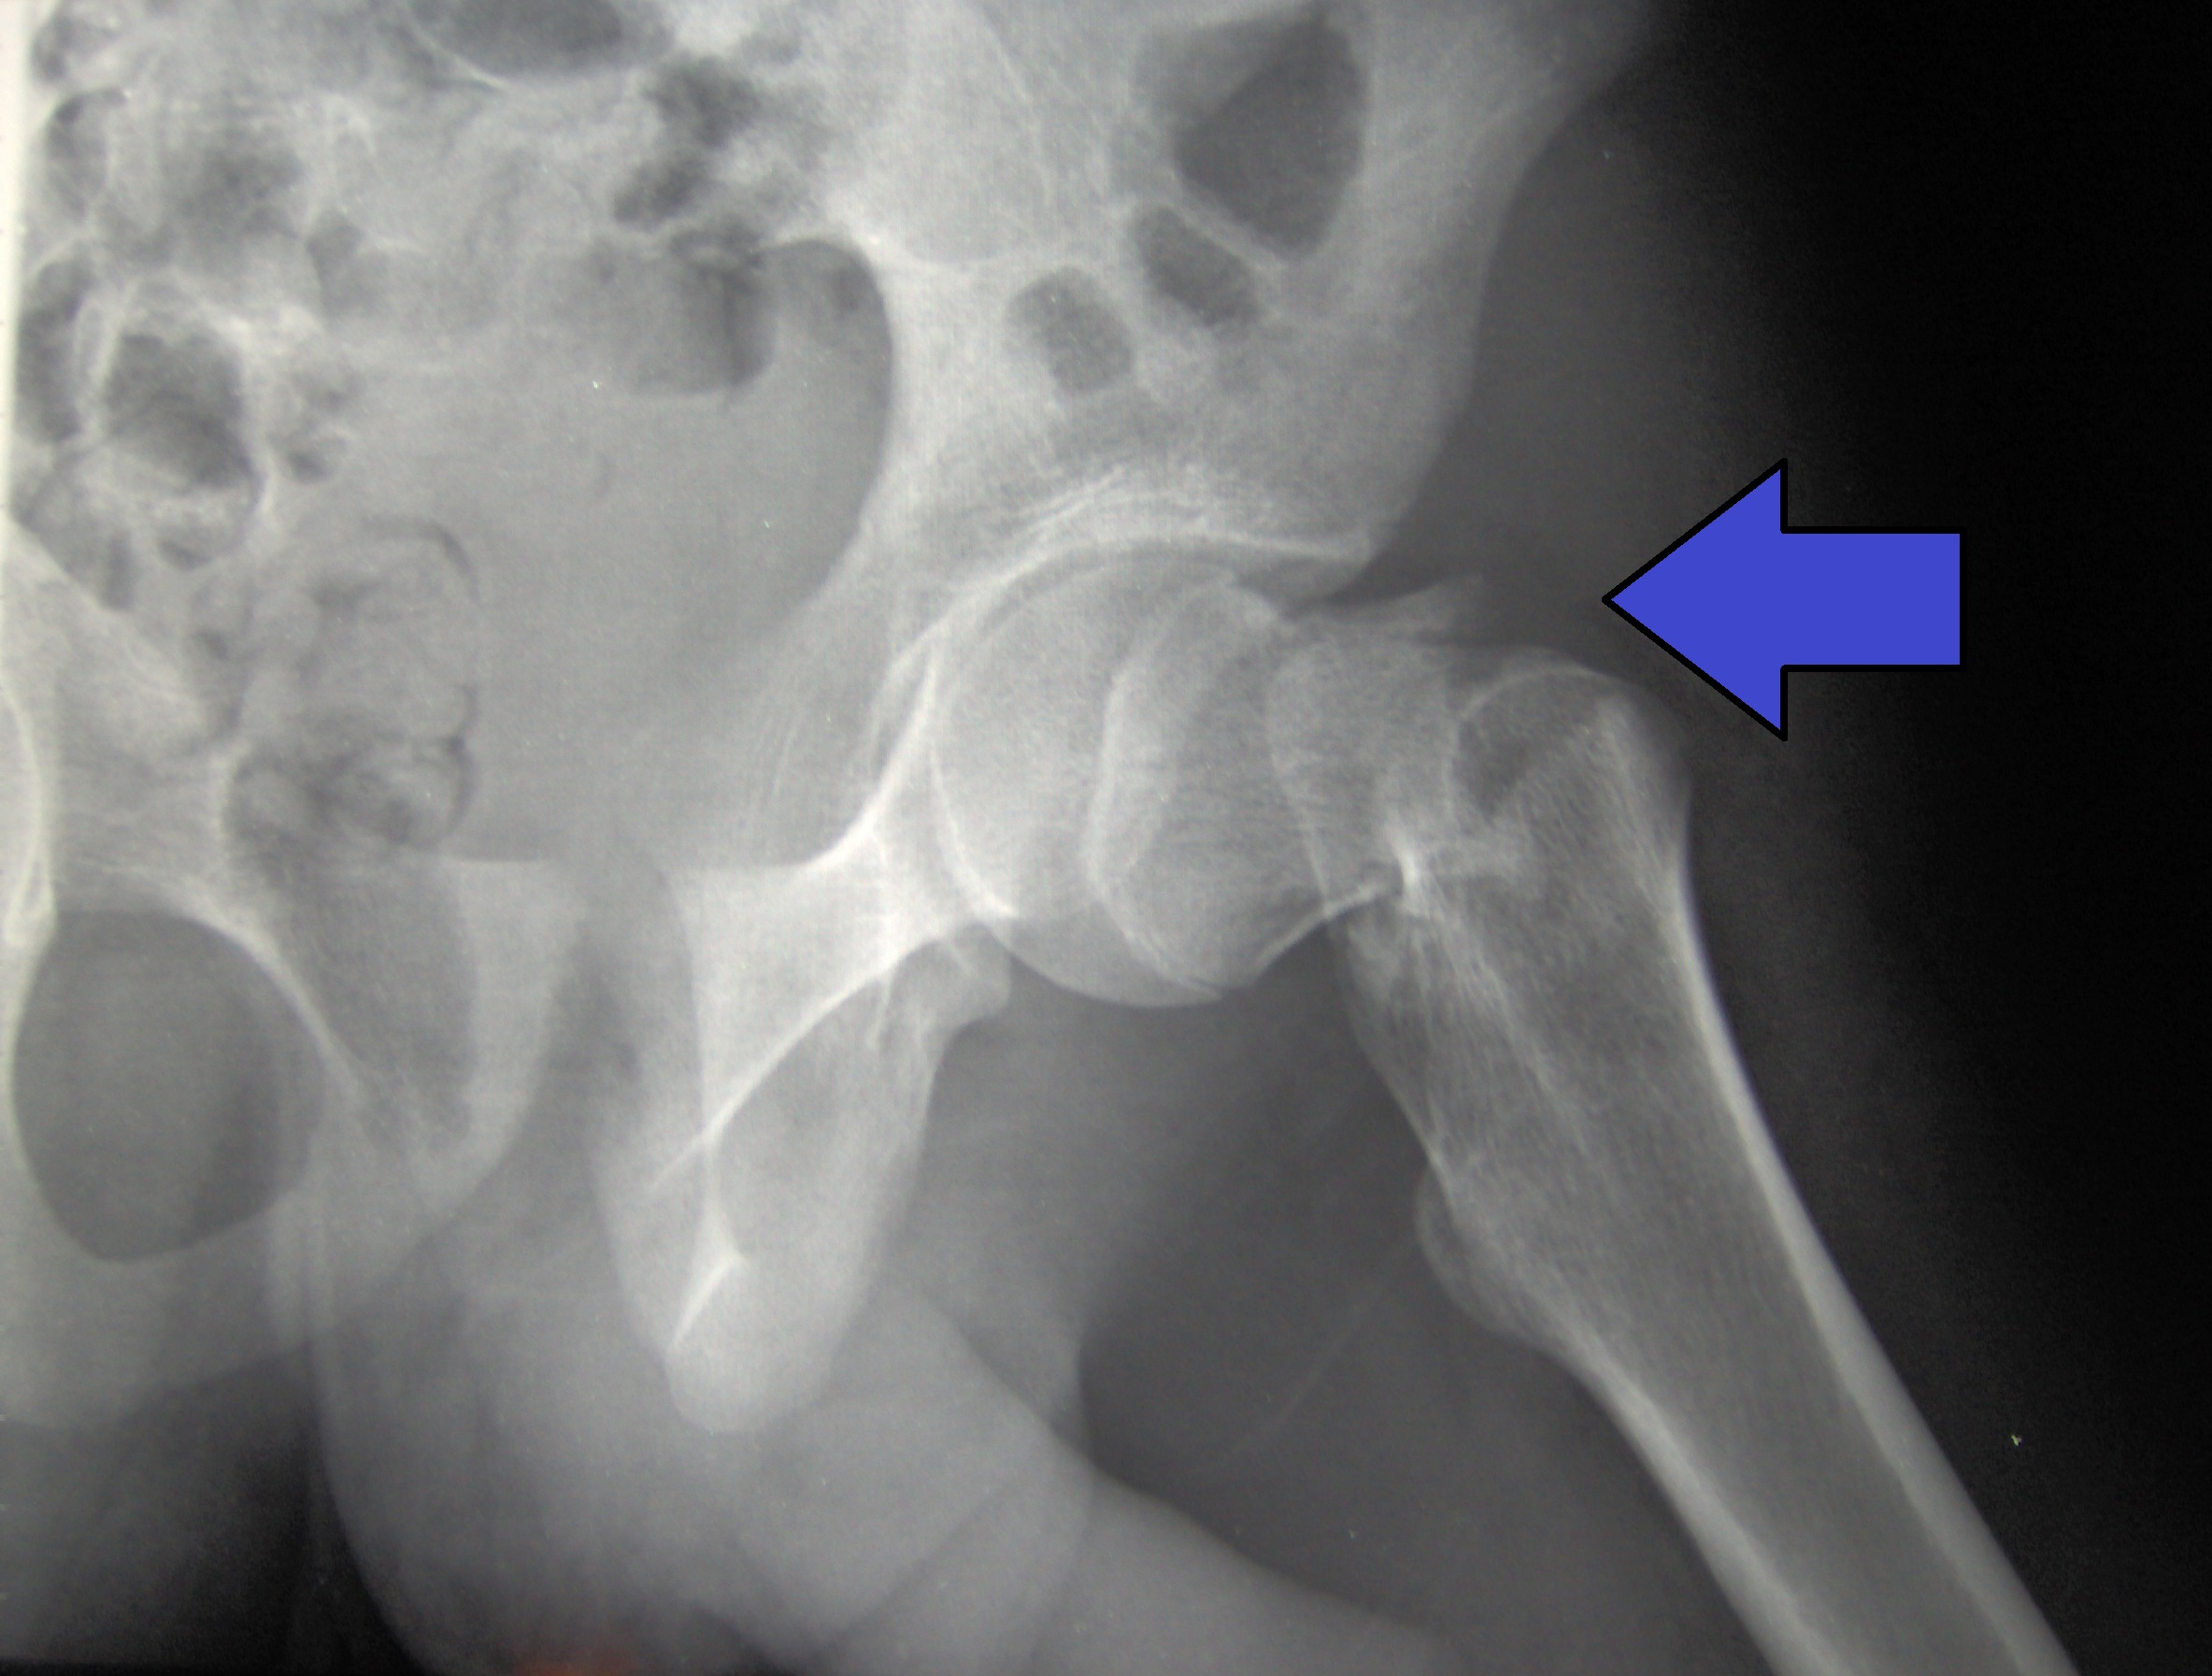

Esta revisión destaca cómo el microambiente óseo responde a concentraciones suprafisiológicas de glucocorticoides y analiza las bases de la fragilidad esquelética y las fracturas. Revisa el uso y las limitaciones de las tecnologías de imagen y las herramientas de predicción actuales y emergentes, y analiza las estrategias de tratamiento osteoformador y antirresortivo, así como su uso para prevenir y tratar la osteoporosis inducida por glucocorticoides. Lancet Diabetes Endocrinol, 26 de septiembre de 2025